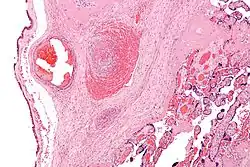

Skeleton

For bones to attain their normal shape and size, they require the stresses from normal musculature.[30] People with cerebral palsy are at risk of low bone mineral density.[31] The shafts of the bones are often thin (gracile),[30] and become thinner during growth. When compared to these thin shafts (diaphyses), the centres (metaphyses) often appear quite enlarged (ballooning).[32] Due to more than normal joint compression caused by muscular imbalances, articular cartilage may atrophy,[33]: 46 leading to narrowed joint spaces. Depending on the degree of spasticity, a person with CP may exhibit a variety of angular joint deformities. Because vertebral bodies need vertical gravitational loading forces to develop properly, spasticity and an abnormal gait can hinder proper or full bone and skeletal development. People with CP tend to be shorter in height than the average person because their bones are not allowed to grow to their full potential. Sometimes bones grow to different lengths, so the person may have one leg longer than the other.[34][35]

Children with CP are prone to low trauma fractures, particularly children with higher Gross Motor Function Classification System (GMFCS) levels who cannot walk. This further affects a child's mobility, strength, and experience of pain, and can lead to missed schooling or child abuse suspicions.[30] These children generally have fractures in the legs, whereas non-affected children mostly fracture their arms in the context of sporting activities.[36]

Hip dislocation and ankle equinus or plantar flexion deformity are the two most common deformities among children with cerebral palsy. Additionally, flexion deformity of the hip and knee can occur. Torsional deformities of long bones such as the femur and tibia are also encountered, among others.[17][37] Children may develop scoliosis before the age of 10 – estimated prevalence of scoliosis in children with CP is between 21% and 64%.[38] Higher levels of impairment on the GMFCS are associated with scoliosis and hip dislocation.[17][39] Scoliosis can be corrected with surgery, but CP makes surgical complications more likely, even with improved techniques.[38] Hip migration can be managed by soft tissue procedures such as adductor musculature release. Advanced degrees of hip migration or dislocation can be managed by more extensive procedures such as femoral and pelvic corrective osteotomies. Both soft tissue and bony procedures aim at prevention of hip dislocation in the early phases or aim at hip containment and restoration of anatomy in the late phases of disease.[17] Equinus deformity is managed by conservative methods especially when dynamic. If fixed/static deformity ensues surgery may become mandatory.[37]